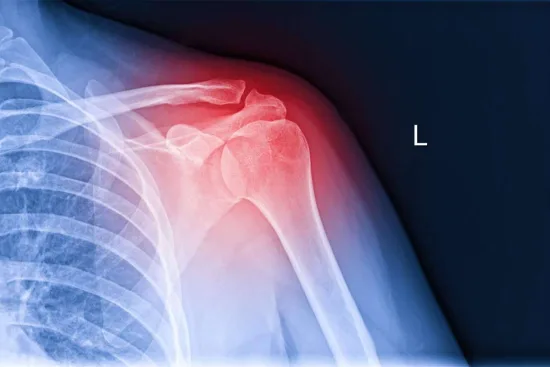

Uno de los más frecuentes ocurre en el manguito rotador. Este es un conjunto de músculos y tendones que se encargan de darle movilidad y estabilidad al hombro. Por lo que, cuando sufre una lesión, el paciente manifiesta un dolor sordo que le impide realizar labores sencillas como tomar un vaso de agua, vestirse, etc.

Adicionalmente, realiza una exploración física para valorar la movilidad del paciente y la estabilidad de los tendones. Dependiendo de los resultados de dicho procedimiento, puede solicitar radiografías, ecografía o resonancia magnética para obtener una visión más amplia del problema. Todos estos aspectos le ayudarán a tener un diagnóstico preciso para luego suministrar el tratamiento indicado para cada paciente.